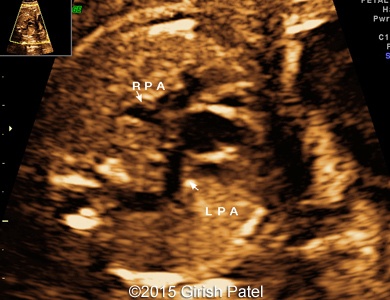

Following images and videos show a case of double inlet left ventricle with transposition of the great arteries that was seen at 26 and 36 weeks of otherwise non-complicated pregnancy.

Images 1, 2, 3, and 4: 2D images showing transverse scan of the heart with double inlet left ventricle and transposition of the great arteries. Following structures can be seen: dominant enlarged left ventricle (LV); diminutive right ventricle (RV) connected to the left ventricle via small bulboventricular foramen; both, left atrium (LA), and right atrium (RA) open to the left ventricle via separate tricuspid and mitral valves; foramen ovale flap can be seen within the left atrium; enlarged pulmonary artery (PA) arises from the left ventricle; small part of the aorta (Ao) arising from the diminutive right ventricle can be also seen.

Images 8, 9, 10: 2D gray scale and color Doppler images showing the heart with double inlet left ventricle and transposition of the great arteries - the images 8 and 9 show mitral and tricuspid valves opened to the left ventricle. The image 10 shows branching of the pulmonary artery (RPA, LPA), arising from the dominant left ventricle.